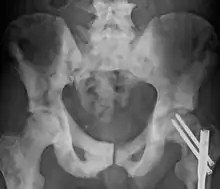

Ostéosclérose du pelvis due à un cancer.

L’ostéosclérose est une affection osseuse qui se caractérise par un accroissement de la densité osseuse trop importante. Elle survient souvent à la suite d'une lésion ou d'une fracture de l'os, mais peut également être causée par des inflammations osseuses, un cancer des os ou par l'arthrose.